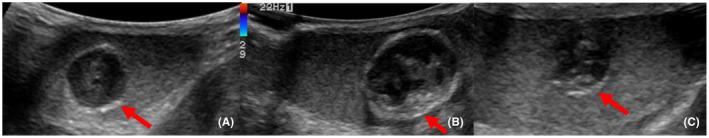

Testicular epidermoid cysts have characteristic findings. Testicular tumor markers are negative in patients with epidermoid cysts. Clear margins and sole and small testicular tumors (20 mm or less) suggest the possibility of epidermoid cyst. Testicular-sparing surgery with intraoperative frozen section examination should be performed when suspecting epidermoid cysts. Testicular epidermoid cysts are rare tumors that account for 1% of all testicular tumors and are often clinically misdiagnosed as malignant lesions. We report three cases of epidermoid cysts. The chief manifestations were scrotal induration in two patients and pruritus scrotum in one. The median age of the patients was 23 years (18-30). All tumors were determined to be sole lesions (<20 mm in diameter). Testing for tumor markers in all patients revealed negative results. We could not rule out malignancy; hence, we performed high inguinal orchiectomy in all cases. Histologically, the inner walls of the cysts were lined with stratified squamous epithelium; their contents were keratinized. All patients were diagnosed with epidermoid cysts.

睾丸表皮样囊肿有特征性表现。表皮样囊肿患者的睾丸肿瘤标志物为阴性。边界清晰且为单发的小睾丸肿瘤(20毫米或更小)提示表皮样囊肿的可能性。怀疑为表皮样囊肿时,应进行保留睾丸手术并术中进行冰冻切片检查。睾丸表皮样囊肿是罕见肿瘤,占所有睾丸肿瘤的1%,临床上常被误诊为恶性病变。我们报告3例表皮样囊肿病例。主要表现为2例患者阴囊硬结,1例患者阴囊瘙痒。患者的中位年龄为23岁(18 - 30岁)。所有肿瘤均为单发病变(直径<20毫米)。所有患者的肿瘤标志物检测结果均为阴性。我们不能排除恶性肿瘤;因此,所有病例均进行了高位腹股沟睾丸切除术。组织学检查显示,囊肿内壁衬有复层鳞状上皮;其内容物为角质化物质。所有患者均被诊断为表皮样囊肿。